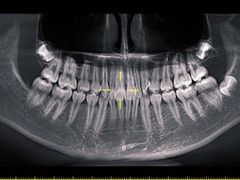

• Dr.Z dental仁康种植矫正中心

• -Dr.Z dental仁康种植矫正中心

抖掉渣 | 22-08-17

报错